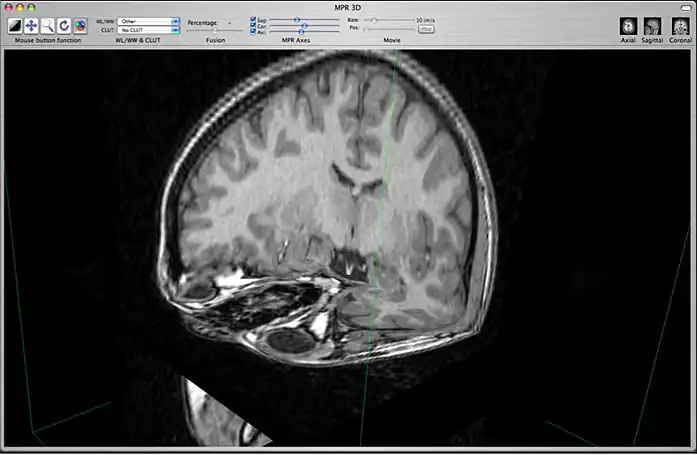

c) 3D Orthogonal MPR

3D orthogonal MPR mode

This mode allows you to display a 3D representation of the volume with 3D orthogonal MPR slices. You can change the position of the orthogonal slices by using the 3 sliders located in the toolbar: